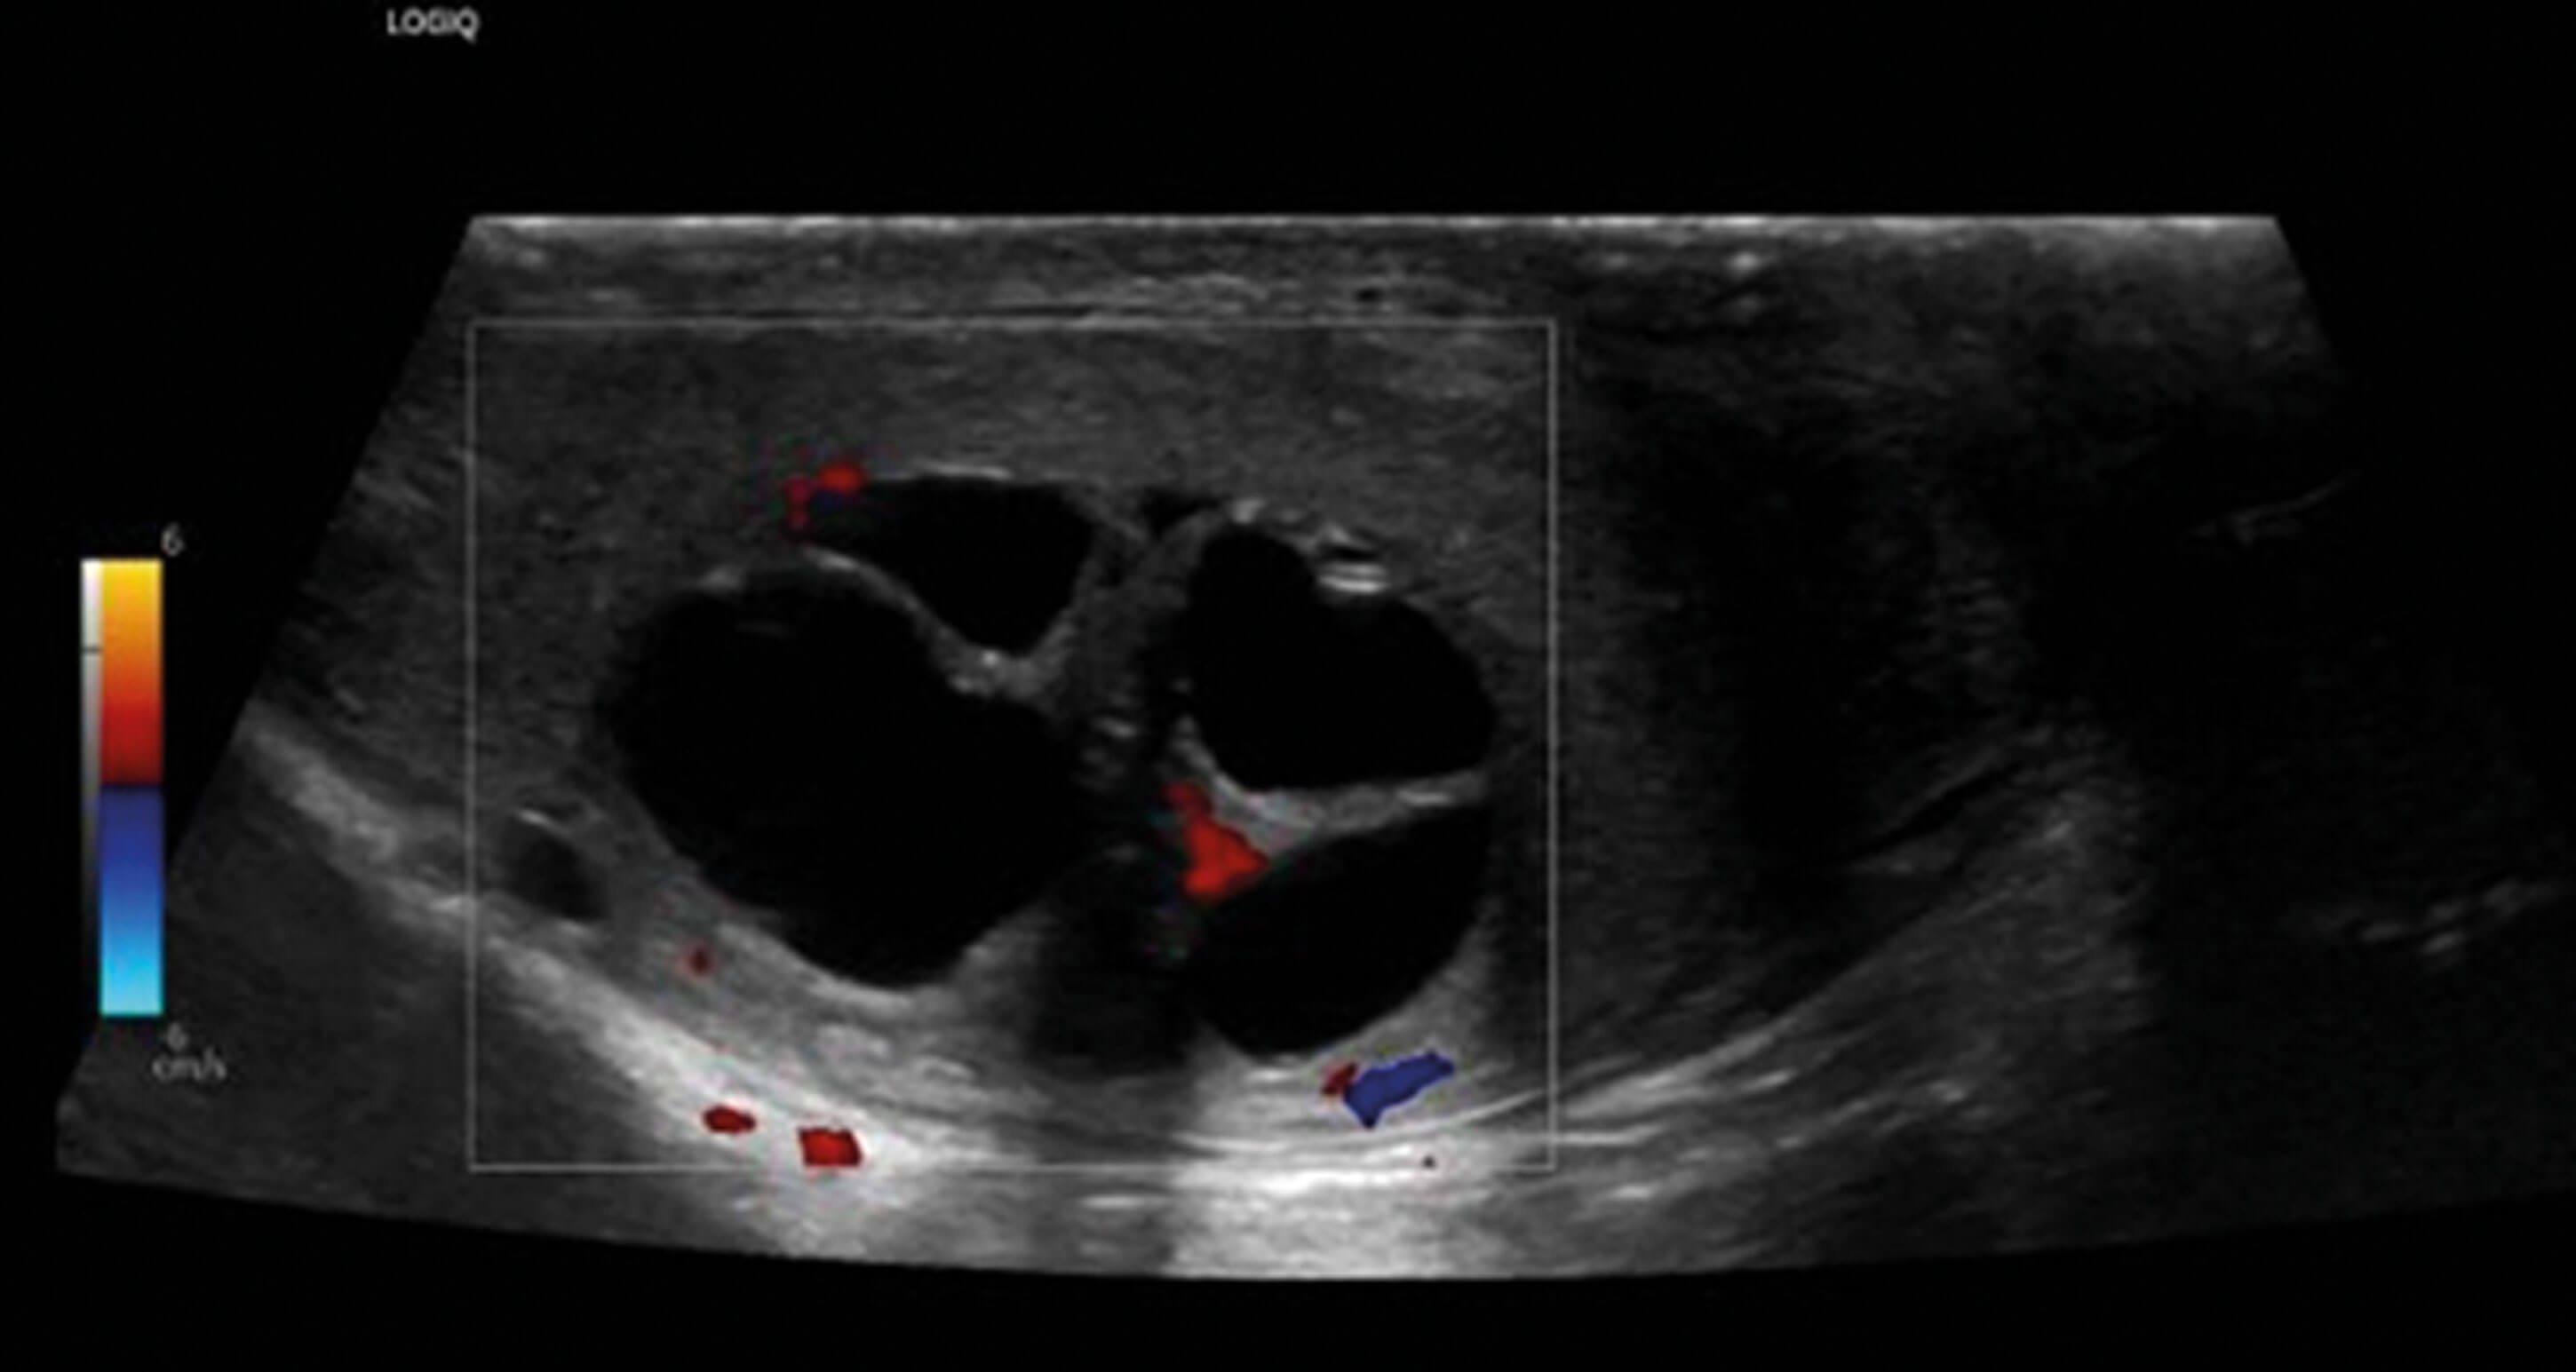

A biopsy of the liver was organised and the patient referred to urology for management of the hydronephrosis. US testes was requested on urological advice which showed a multiloculated cystic mass containing thick internal septations and internal vascularity, typical for choriocarcinoma (Figure 7). Liver biopsy confirmed the diagnosis and subsequent β-HCG was found raised at 225,383mIU/mL. The patient was transferred urgently to a specialist centre for inpatient chemotherapy. He responded well and treatment is ongoing.

Figure 7: Multiloculated cystic mass of right testicle containing thick internal septations and demonstrating internal vascularity.